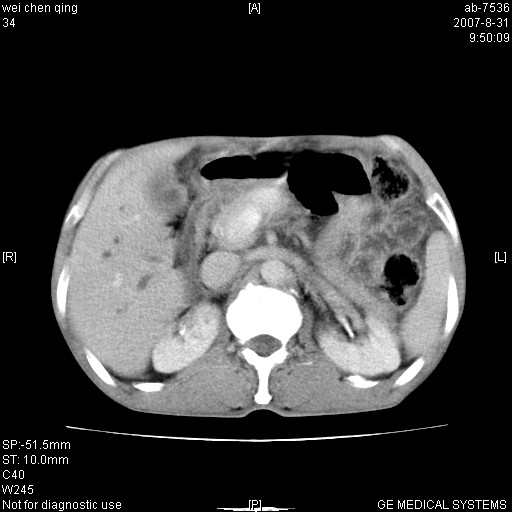

以下是引用zjzjr在2007-8-31 14:38:00的发言:[br]胰头癌伴肝内胆管扩张可能性大。

以下是引用zyyzzy在2007-8-31 14:34:00的发言:[br]该病人肝内胆管扩张,胆囊及胆总管未见明显扩张。在倒数第9层图像上可看到左右肝管结合部(肝总管)有软组织影,此处应薄层扫描。考虑肝总管占位(ca)、腹水。[br]